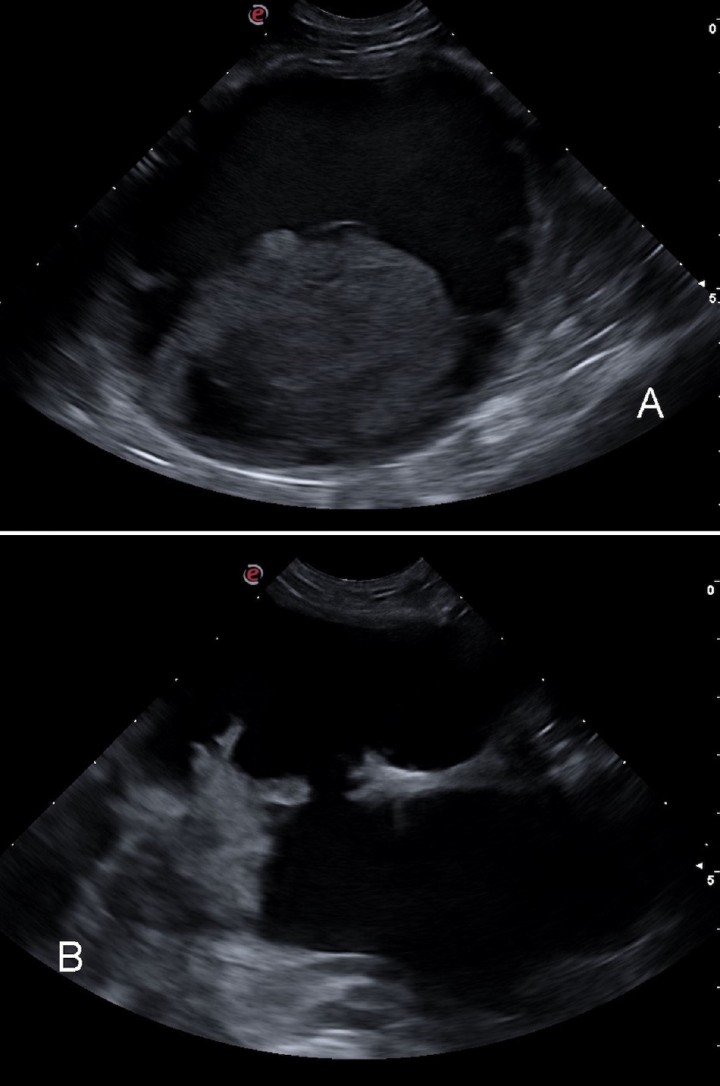

En este caso se realizó una ecografía abdominal en la que se observó un aumento de tamaño y ecogenicidad de la próstata y una estructura de apariencia quística que parecía originarse de la misma y que seguía un crecimiento en dirección laterocraneal. Dicha estructura presentaba unas dimensiones aproximadas de 5 x 7 cm y, en su interior, contenido ecogénico, por lo que podía ser compatible con un quiste o absceso prostático o quiste paraprostático. Además, se visualizaron otras dos estructuras de apariencia quística craneales a la próstata de 7 x 8 cm y 5 x 6 cm, respectivamente, con contenido líquido hipoecogénico así como una estructura ecogénica redondeada dentro (Fig. 3A). En el interior de la zona perineal izquierda se visualizó una estructura quística con contenido anecógeno (Fig. 3B).

<p>Imágenes ecográficas de los quistes paraprostáticos. (<strong>A</strong>) Corte longitudinal de un quiste abdominal con contenido hipoecogénico y centro ecogénico. (<strong>B</strong>) Corte transversal de quiste paraprostático en la zona perineal, con contenido anecógeno en su interior.</p>

Figura 3

Imágenes ecográficas de los quistes paraprostáticos. (A) Corte longitudinal de un quiste abdominal con contenido hipoecogénico y centro ecogénico. (B) Corte transversal de quiste paraprostático en la zona perineal, con contenido anecógeno en su interior.

El estudio ecográfico de la cavidad abdominal fue compatible con presencia de quistes paraprostáticos, quistes o abscesos prostáticos, granulomas, hematomas o, con menor probabilidad, neoplasia prostática. Con respecto a la zona perineal, las imágenes ecográficas fueron compatibles con un desplazamiento caudal y protrusión hacia la zona perineal de un quiste paraprostático.[ Dennis R, Kirberger R.M, Barr F, Wrigley R.H. Handbook of Small Animal Radiology and Ultrasound. Saunders. Elsevier. Second edition. Croydon (UK), 2010; 255-262. ]